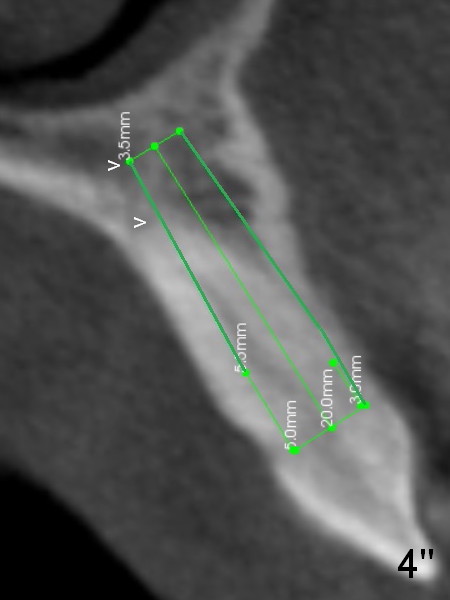

Lengthwise, a longer osteotomy is needed (Fig.4): 20 mm at the gingival level, 17 mm at the bone level. Distal to the 5 mm tap is a gap (*). Initially a shorter osteotomy (by 3 mm) is made: there is minimal engagement with the labial bone (Fig.4' between arrowheads (CT coronal section from not the same patient)). The osteotomy is extended (Fig.4''). This is the second problem to be solved.